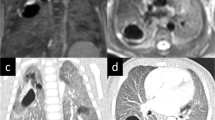

Results from the structured CT and MRI reports are shown in Tables 2 and 3, and Fig. 3. Between postnatal CT and school-age MRI, the appearance and diagnostic interpretation of the type of CLA changed in 7 patients of the unoperated group (41%). In three patients, the lesion was classified as a CPAM on postnatal CT and as a BA on school-age MRI, and in one patient a mixed lesion (CPAM and BA) was seen on postnatal CT, and only a BA was found on school-age MRI. In addition, in three patients, the solid component of the lesion classified as a hybrid lesion (n = 1) or BPS (n = 2) appeared as cystic tissue on school-age MRI. Example images of changing appearances of CLA between postnatal CT and school-age MRI are shown in Fig. 4.

Example images of changed appearance of CLA between postnatal CT and school-age MRI. Patient 1: axial postnatal CT showing an air-filled multicystic CPAM and BA in the left lower lobe (a) and an axial T2-weighted PROPELLER image at school-age showing only BA in the left lower lobe (arrow) (b). Patient 2: axial postnatal CT showing an air-filled CPAM surrounded by lesion-associated parenchymal atelectasis (asterisk) (a) and an axial SPGR expiratory image at school-age showing an air-filled CPAM without lesion-associated parenchymal abnormalities (b)